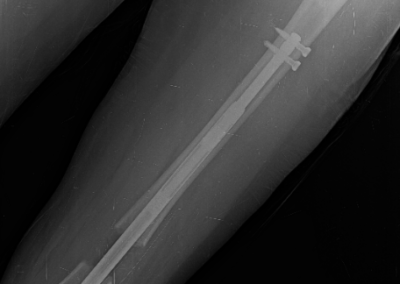

Lengthening SurgeryDec 30, 2021 | Case Examples Case 1: Tibiada Extension Over Nail (LON) Case 2: Femurda Extension Over Nail (LON Case 3: Femurda Automatic Nail Extension